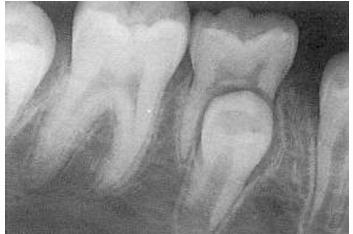

-anomaly: ankylosis

-fusion

-concrescence: cementum fuses together

-unfavorable resorption pattern of roots